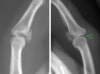

X-ray : 중간 지골 골절(middle phalanx fracture)